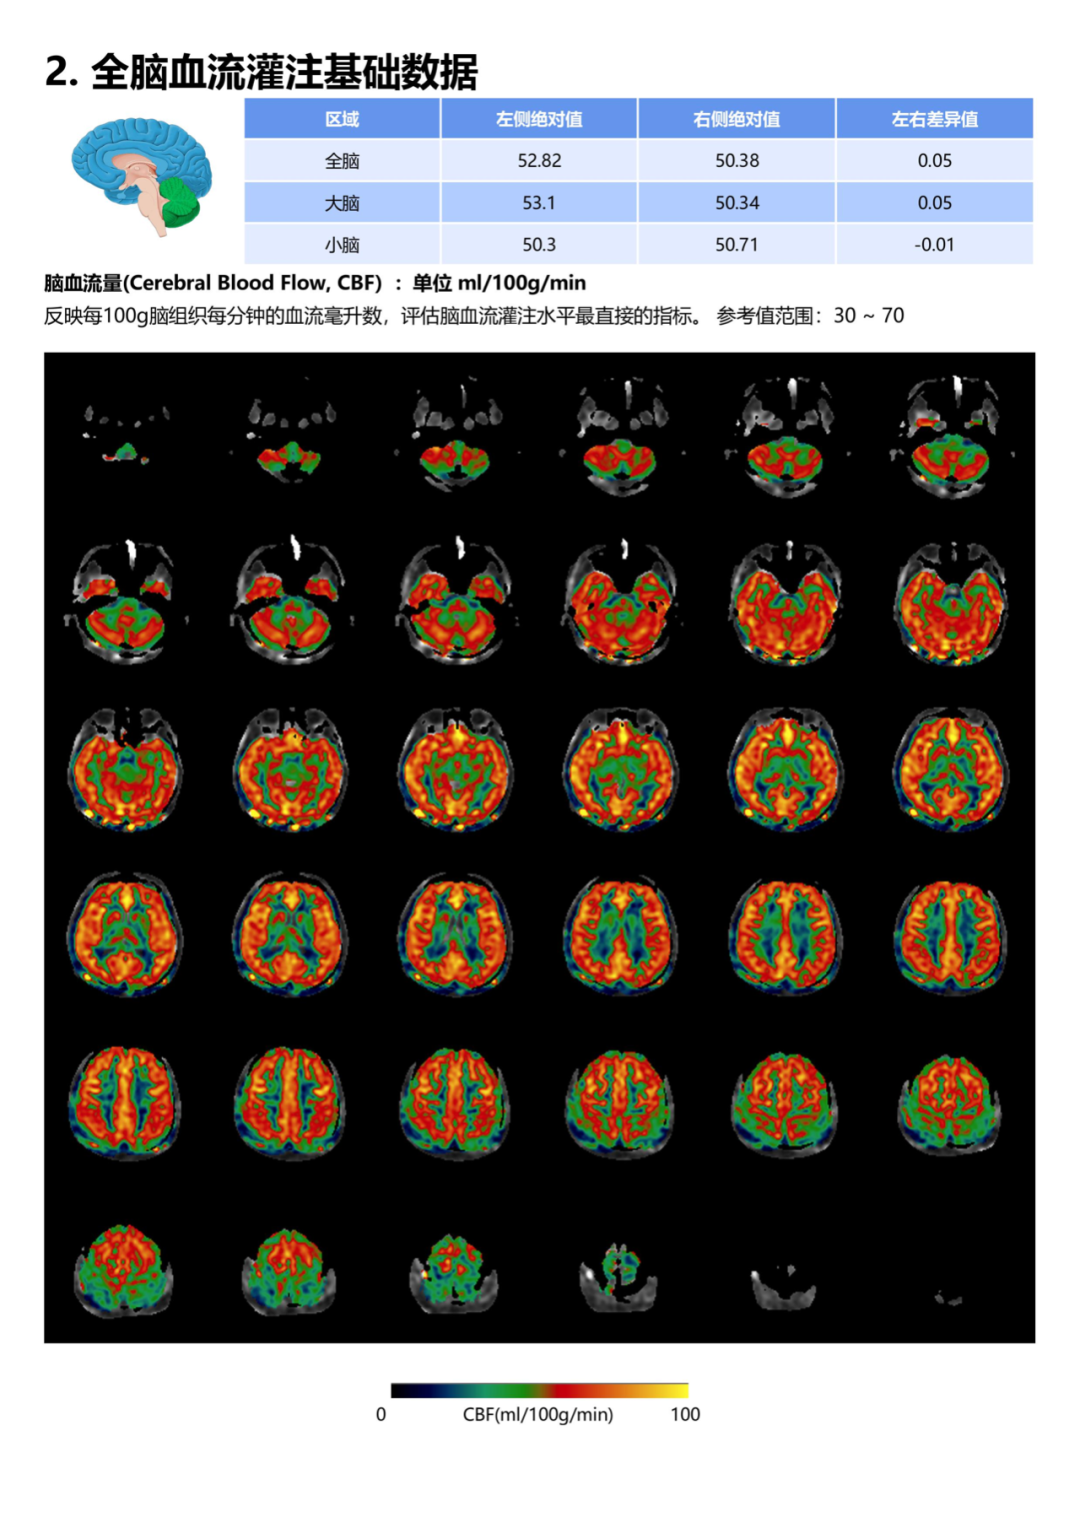

脑灌注[s0]脑灌注与认知功能障碍(脑灌注概念)[s1]ct脑灌注原理及临床应用[s2]脑灌注是什么意思 来自搜狐网[s3]脑灌注[s4]PPT 注释 | 脑灌注成像(DSC)的临床应用(1)--李润涛[s5]脑灌注:xe-ct评价脑血流量指导扩容 2.5 xe-ct de the decision to p[s6]脑灌注是怎么做的,是多个序列,根据序列时间分析血流?#码农的日常# 多个心脏序列的连续渲染就是跳动效果[s7]文献编译| 儿童烟雾病脑灌注成像 磁共振asl与pet比较[s8]图片[s9]PPT 注释 | 脑灌注成像(DSC)的临床应用(1)--李润涛[s10]Image[s11]关于什么是ct脑灌注成像?你一定要知道这些知识![s12]基于动脉自旋标记技术的帕金森病伴抑郁患者脑灌注研究[s13]神经影像| 无需注射造影剂的脑灌注成像:磁共振asl技术进展及应用[s14]渭南市第二医院医学影像科颅脑cta脑灌注ctp(一站式成像新突破)[s15]【请您关注】总院云影像中心顺利开展ct脑灌注成像检查[s16]asl脑部灌注的原理及临床应用[s17]Image[s18]文献编译| 儿童烟雾病脑灌注成像 磁共振asl与pet比较[s19]Image[s20]ppt+注释 | 脑灌注成像(dsc)的临床应用(1)--李润涛[s21]渭南市第二医院医学影像科颅脑cta脑灌注ctp(一站式成像新突破)[s22]软件试用| 无创脑灌注定量成像3d-asl后处理[s23]脑灌注(ctp):提示左侧额颞顶部大面积灌注不足.[s24]脑灌注成像检查,您了解多少?[s25]图片[s26]核磁脑灌注图显示右侧枕顶颞缺血[s27]图片[s28]脑灌注是什么意思 个人图书馆[s29]神经影像| 脑灌注成像磁共振asl技术基本原理及临床应用(一)[s30]「夜班不求人」解读ct脑灌注[s31]图片3.jpg[s32]烟雾病患者ct全脑灌注成像及cta检查影像学特征及临床应用[s33]脑灌注是什么意思 头条[s34]PPT 注释 | 脑灌注成像(DSC)的临床应用(1)--李润涛[s35]ppt+注释 | 脑灌注成像(dsc)的临床应用(1)--李润涛[s36]2. 灌注压的稳态。合理的脑灌注压,是stbi患者术后恢复的重要干预指标,脑[s37]图2: 同侧和对侧脑灌注都有改善.自己的一点体会:我们在临床中经常碰到,[s38]ppt+注释 | 脑灌注成像(dsc)的临床应用(1)--李润涛[s39]